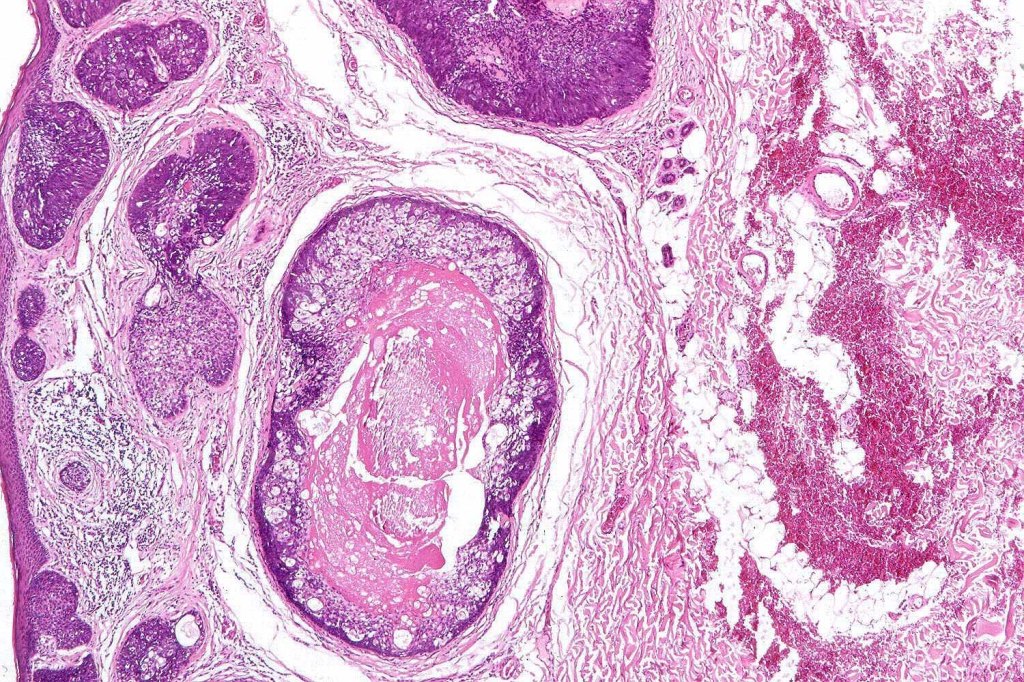

Histological features

•Lobules drain into a dilated follicle

•Lobules are increased in number but do not differ in structures from normal sebaceous glands

•Sebaceous hyperplasia is not associated with Muir-Torre syndrome